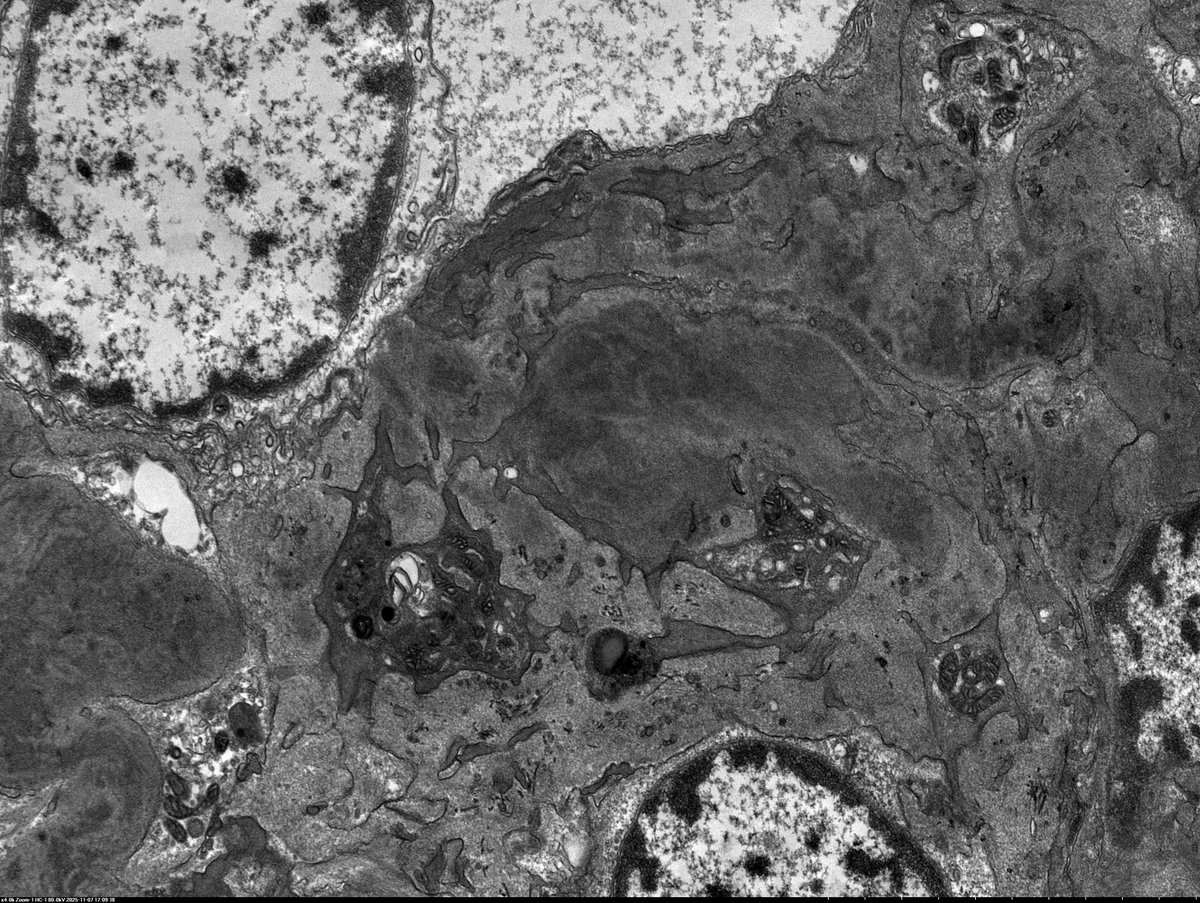

C3 GN in 11 yo boy with proteinuria, hypertension, low C3 (normal C4). EM shows irregular thickening of glomerular capillary wall and mesangial expansion by electron dense deposits. The deposits are somewhat ill-defined with early sign of resorption.